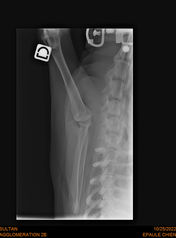

Joey wurde erfolgreich operiert, jetzt macht er fleißig Physio und dann denken wir kein sein Leben beginnen

Joey ist ein junger Cocker Rüde, den wir in seiner Not aufgenommen haben. Da der kleine Genosse öfters mal mit seinen Zähnen versucht seinen Willen durchzusetzen und dazu noch einen alten Schulterbruch hatte, war er einer der Nächsten, der eingeschläfert worden wäre.